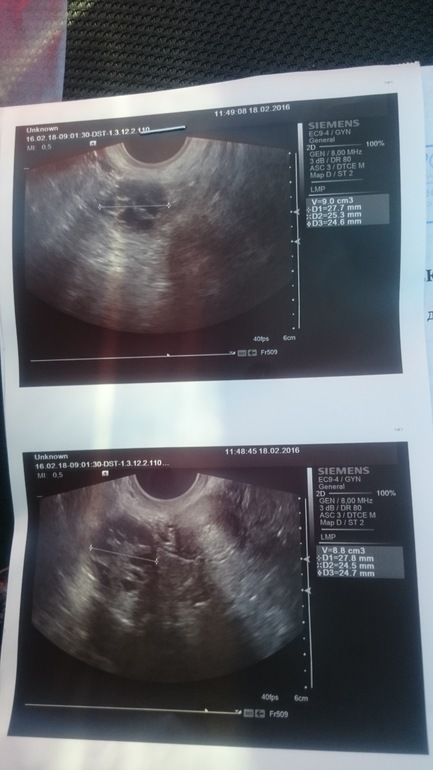

А имеем мы 23 ДЦ и:

Да, это мой поликистоз, привет блин!

Делала в этом цикле УЗИ три раза (на 6 дц, на 13 дц и вот на 23), с каждым разом поликистоз увеличивался, вернулся. А покидал он меня на пол цикла благодаря сильно повышенному прогестерону, в следствии О на 5 дц).